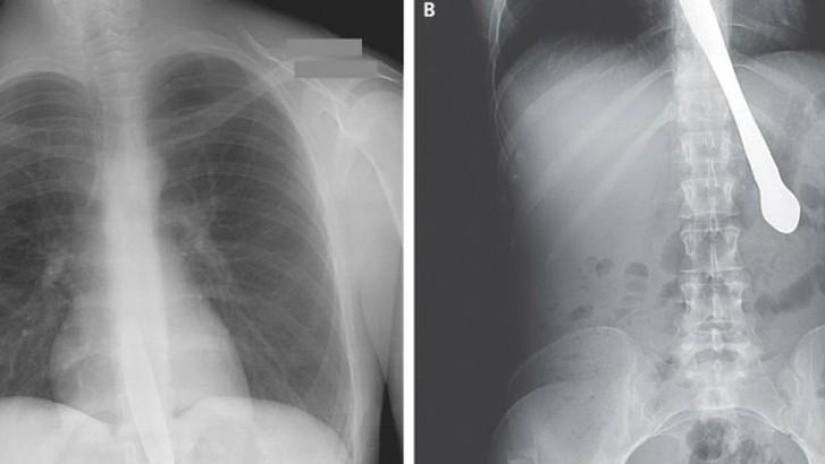

22. Surgical forceps.